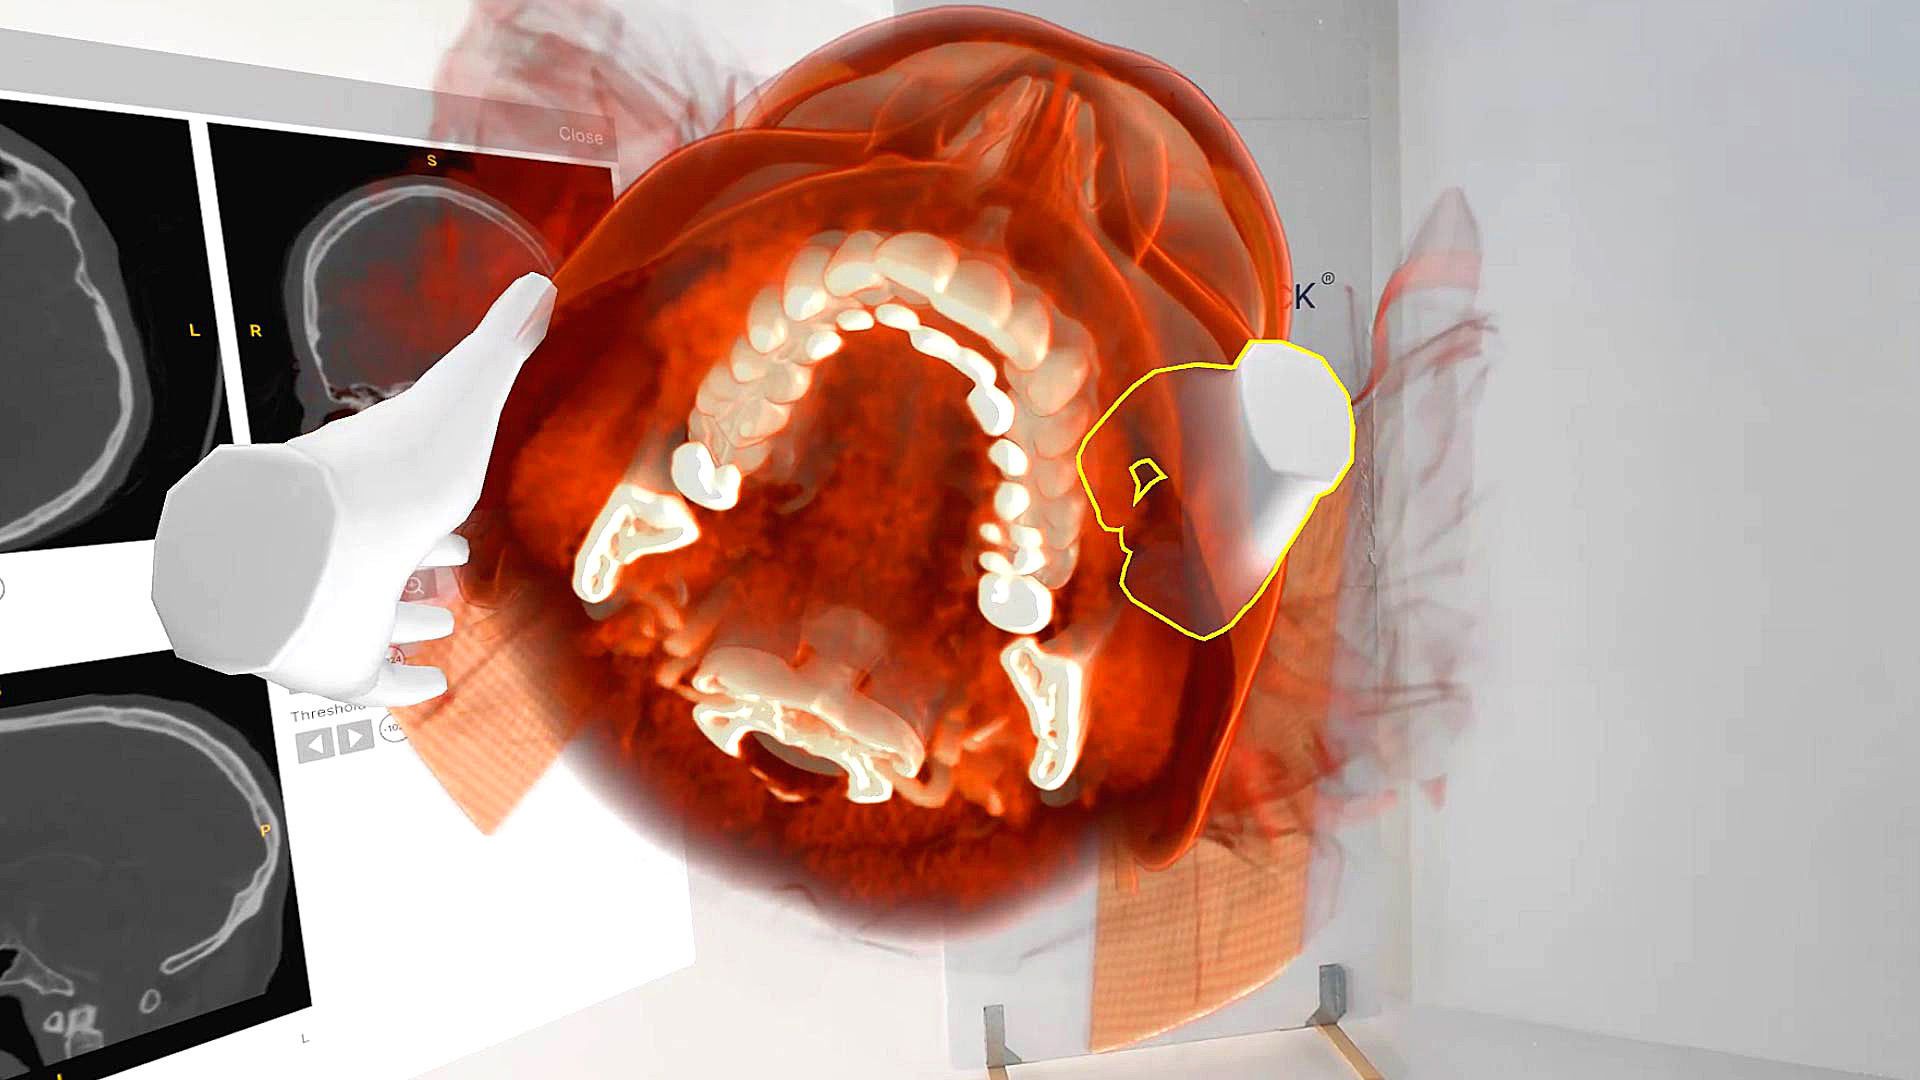

A groundbreaking approach to tackling complex lacrimal obstructions.

Endoscopic dacryocystorhinostomy in posttraumatic nasolacrimal duct obstruction.

Endoscopic dacryoplasty (DCP) for failed dacryocystorhinostomy (DCR) in granulomatosis with polyangiitis (GPA).

Virtual reality and telemedicine in endoscopic procedures for treatment of lacrimal drainage obstruction.